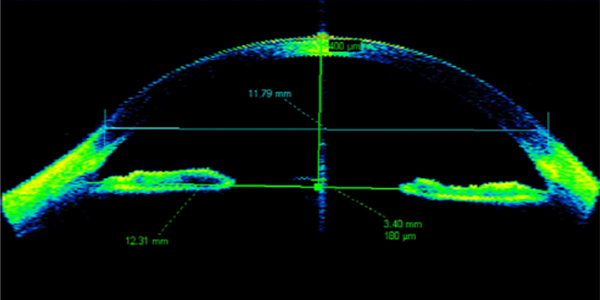

재수술 가능한 400㎛, 각막 상피 두께 검사로 잠재된 원추각막을 진단합니다.

ICL 렌즈삽입술 전후 각막 전안부 CT